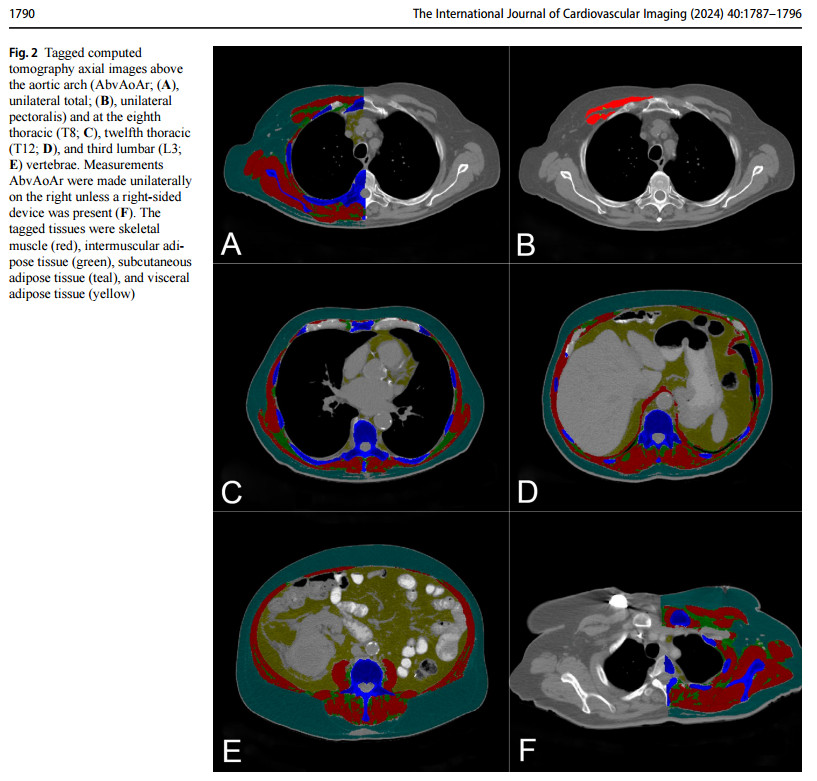

Automated Body Composition Measurement and Outcomes

• Improving the value of imaging in chronic disease evaluation by "opportunistically" quantifying patterns of muscle loss, fat loss, and paradoxical relationships between subtypes of obesity and survival using CT imaging.

• Two funded grants and >10 coauthored peer-reviewed manuscripts showed body composition is an independent predictor for outcomes of aortic disease, severe heart failure, non-Hodgkins lymphoma, breast cancer.